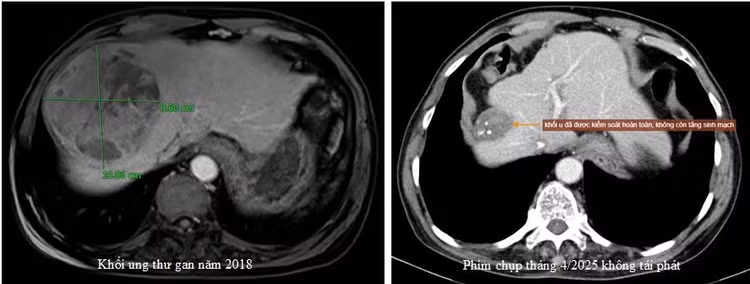

Trường hợp điển hình là người bệnh A.V.Q, 74 tuổi, ở Cẩm Khê – Phú Thọ, phát hiện ung thư gan với kích thước 10cm, đã được nút mạch sử dụng kỹ thuật TACE.

tace-3.jpg

Sau 4 lần thực hiện nút mạch từ năm 2018 đến 2022, duy trì thăm khám, theo dõi thường xuyên, đến nay khối u của bệnh nhân đáp ứng tốt và teo nhỏ, không có sự tái phát - Ảnh BVCC